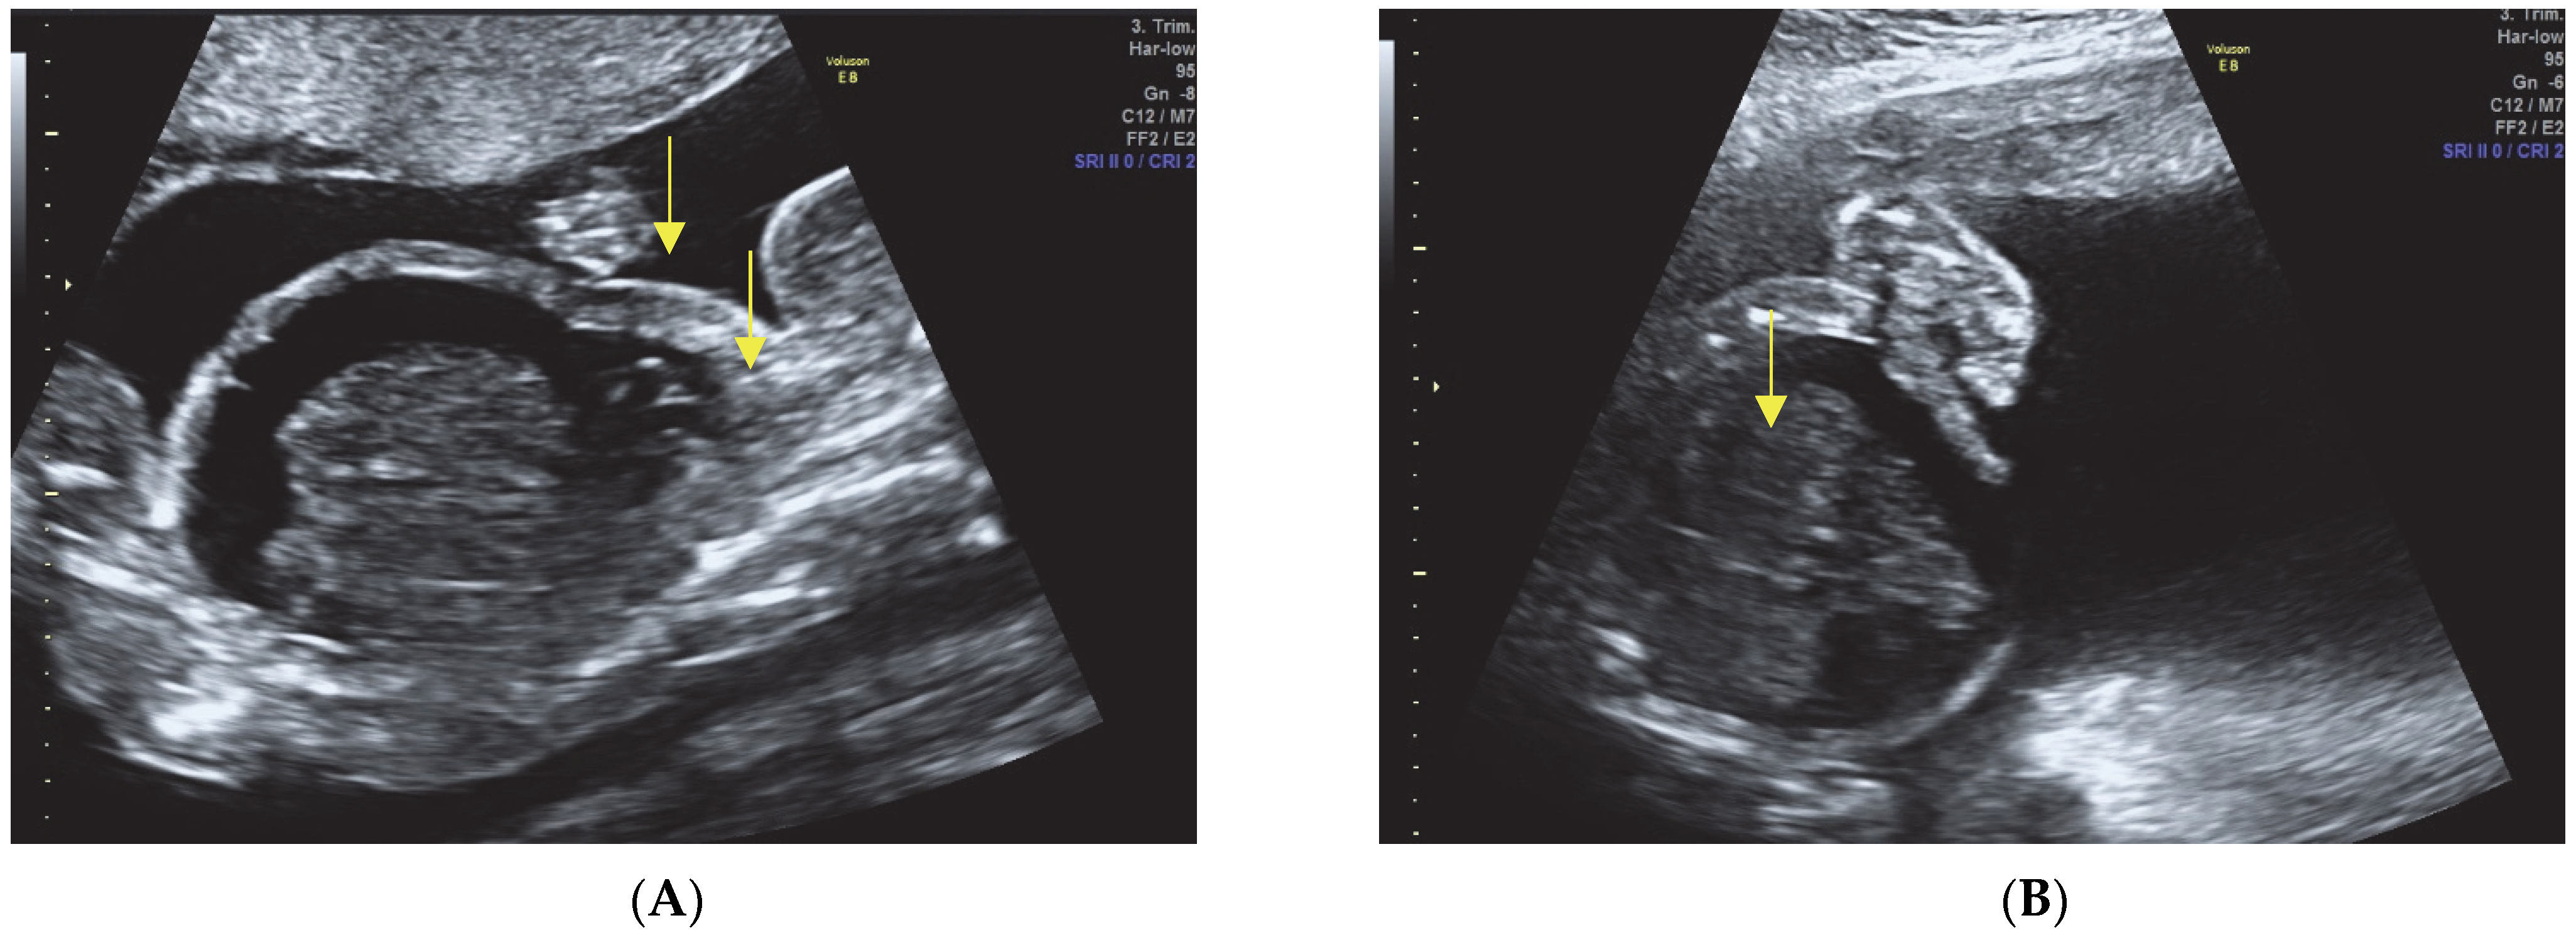

- Hypomineralization of the skull bones.

- Narrow thorax with evidence of pulmonary hypoplasia.

- Presence of fetal hydrops, characterized by ascites, pleural effusion, and subcutaneous edema.